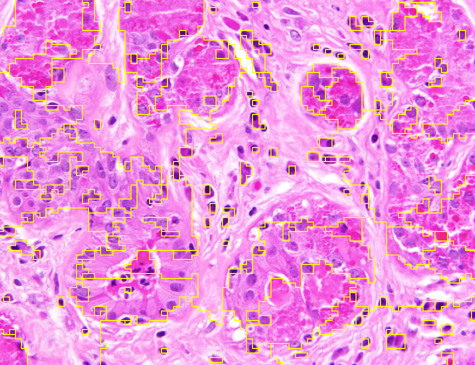

Representative samples from the three datasets are shown in Fig. 1. In (a), the first frame of the synthetic video in Dataset 1 illustrates the strong illumination gradients produced by distance-dependent shading together with orientation-dependent interactions between vertex normals and the light direction. The H&E images in (b) and (c), also from Dataset 1, depict a mast cell infiltrate from a patient with non-alcoholic steatohepatitis and cirrhosis and, respectively, a sample from a patient with sclerosing polycystic adenosis of the parotid gland; the former consists primarily of purple nuclei, white cytoplasm, and pink extracellular tissue. Subfigures (d) and (e) show two examples from Dataset 2 accompanied by their ground-truth nuclei annotations, while (f) and (g) present a representative image from Dataset 3 together with its corresponding cell mask.

Figure 1: Samples from Datasets 1–3. (a) First frame of the 74-frame video in Dataset 1 (1770 × 880) with a superimposed red mesh. (b,c) H&E-stained tissue images from Dataset 1 (1000 × 750; 950 × 730). (d,e) Cell images from Dataset 2 (600 × 600) with nuclei annotations. (f,g) Image from Dataset 3 (512 × 512) with annotation.

Figure 9 shows the segmentation results for the first hematoxylin and eosin (H&E)–stained image from Dataset 1 (see Fig. LABEL:fig_sub:he1_image). Initial level sets and superpixels are shown in Figs. LABEL:fig_sub:he1_in1_zz-LABEL:fig_sub:he1_in_SP: AR and ZZ used two distinct level sets for nuclei (S1) and cytoplasm (S2) (Figs. LABEL:fig_sub:he1_in1_zz-LABEL:fig_sub:he1_in2_zz), while SP and SMST (Fig. LABEL:fig_sub:he1_in_SP) used the same set of 4000 Power-SLIC superpixels in the same color space (red channel for S1, remaining channels for S2). SAM does not allow separate-channel segmentation; its combined S1/S2 result is shown in Fig. LABEL:fig_sub:he1_out_SAM. Figures LABEL:fig_sub:he1_out1_AR-LABEL:fig_sub:he1_out1_SP display S1 results for AR, ZZ, SMST, and SP, and Figs. LABEL:fig_sub:he1_out2_AR-LABEL:fig_sub:he1_out2_SP show the corresponding S2 results.

AR seemed highly sensitive to initialization, segmenting mainly regions near seed points and requiring seeds in nearly all connected foreground components for satisfactory performance. ZZ segmented a wider range of objects from fewer seeds but incorrectly included nuclei in cytoplasm segmentation, failing to capture white regions and introducing spurious tissue. SAM automatically detected many nuclei and some cytoplasm but merged all structures into a single segmentation, limiting its practical utility here. SMST was the fastest but failed to recover large homogeneous regions, such as the background, and frequently fragmented them due to its variance-based metric. In contrast, SP yielded the most accurate results on both S1 and S2, with clear background separation and precise boundary delineation.

Figure 9: Unsupervised segmentation of the image in Fig. LABEL:fig_sub:he1_image for two structures: purple cells (S1) and white cytoplasm (S2). Initializations via level sets (LS) for AR and ZZ are shown in (a, b); 4000 superpixels for SMST and SP in (c) (red channel for S1, remaining channels for S2). SAM does not allow separate-channel segmentation; its overall output is in (d). Results for S1 are in (e–h) and for S2 in (i–l). Computation times (S1/S2, in seconds): AR 829.51/570.32, ZZ 4304.50/4470.56, SMST 0.38/0.38, SP 5.98/4.26; superpixels in (c) computed in 0.17s, SAM in (d) in 7.42s.